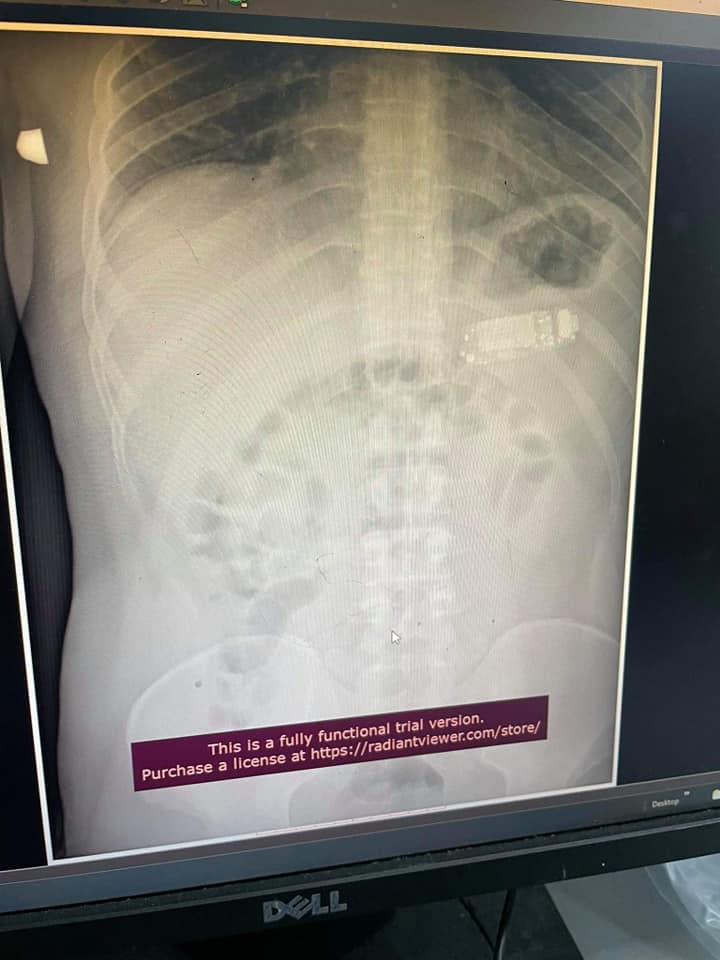

Чоловікові зробили рентген і на знімку дійсно виявили мобільний телефон з кнопками.

Хірургам довелося провести складну операцію і розділити телефон на три частини за допомогою ендоскопії. Сторонній предмет був занадто великим, щоб шлунок міг його переварити. Тим більше пацієнт був в небезпеці - акумуляторна кислота могла витекти та спровокувати сильне отруєння.